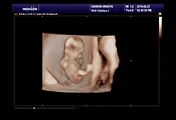

엄마와 아빠의 태교

근데 감기걸려서 훌쩍훌쩍

결국 아빠가 거의 다했다..

결국 완성!